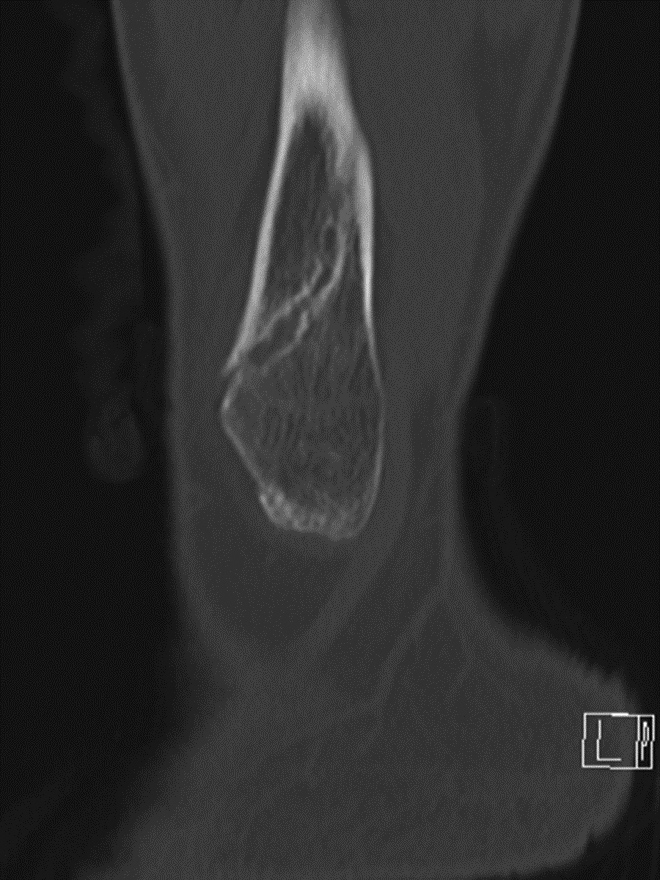

Fracture Union. (A) Sagittal multiplanar reformation demonstrates non-united distal fibular fracture. (B) Follow-up dual-energy CT coronal multiplanar reformation demonstrates distal fibular fracture healing after fixation for non-union.